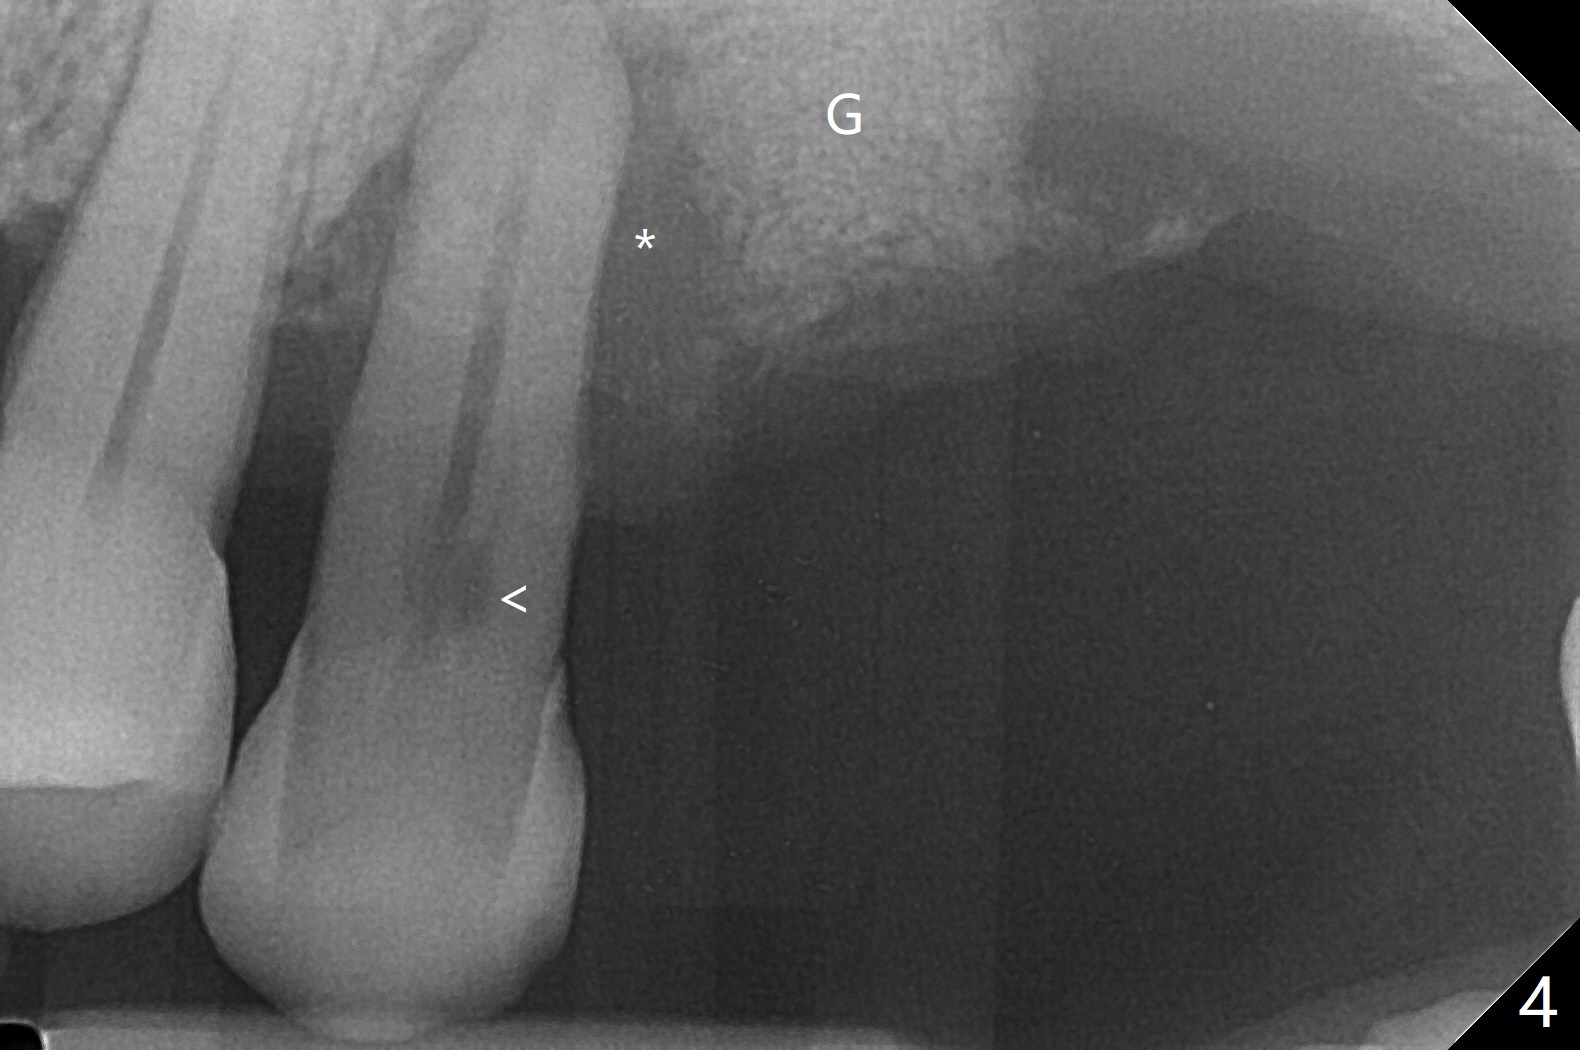

血小板生长因子BB与皮质骨/皮松质骨调合后植入近中颊侧窝(图四G)。今后植牙近远中宽度仿佛不够。13号牙根周阴影(*)是牙髓病(<)还是牙周病?有保留余地吗?图五是另外一张术后即刻根尖片。